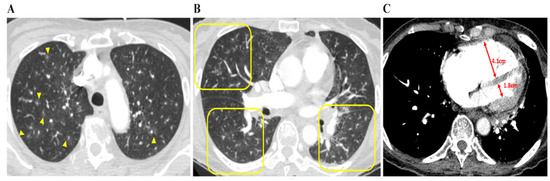

Cardiac enzyme levels concerning troponin T and D-dimer were both high in all nine patients. There were no specific findings other than right-axis deviation on the electrocardiogram. The median interquartile (IQR) D-dimer and N-terminal pro b-type natriuretic peptide (NT-proBNP) levels were particularly high at 16.52 (6.18–25.09) μg/mL and 4237 (3664–8153) pg/mL, respectively (Table 1). Plain chest radiography findings indicated that 50% of the patients had cardiomegaly and enlargement of the pulmonary trunk. Abnormalities of the lung, such as GGOs or interstitial thickening, were observed in only two patients, with most patients showing no new pulmonary lesions. On chest CT, specific findings of PTTM, such as a vascular tree-in-bud sign and centrilobular GGNs were identified in five and eight patients, respectively. In particular, all patients had an RV: LV ratio > 1, indicating RV dilation. Nonspecific findings included peripheral wedge GGOs, interstitial thickening, and consolidation. Except for one patient with a minor subsegmental PTE, all patients were grossly clear of PTE (Table 2, Figure 2).

Figure 2.

Chest CT findings concerning patients with PTTM. A 73-year-old woman with advanced gastric cancer (Case 8). (A) Bilateral lung CT scan results showing disseminated centrilobular GGNs (yellow arrows), (B) in which occasional vascular trees-in-bud signs (yellow squares) are noted. (C) Right and left ventricle (RV and LV) diameters are 4.1 cm and 1.8 cm, respectively, and the RV: LV ratio is 2:3, indicating that RV dysfunction, despite pulmonary arterial thromboembolism is not being depicted. Abbreviations: CT, computed tomography; GGNs, ground-glass nodules; LV, left ventricle; PTTM, pulmonary tumor thrombotic microangiopathy; RV, right ventricle.

Although chest CT and radiography are limited in terms of not being able to directly determine heart function, this study summarized the characteristics of the radiological findings in patients with PTTM. Plain chest radiography findings indicated no lung parenchymal lesions that could cause severe respiratory distress among any of the patients; however, cardiomegaly and pulmonary trunk enlargement were observed in some patients. On chest CT, the RV: LV ratio quantified RV dilation, and all patients had a RV: LV ratio of >1, confirming RV dilatation regardless of whether the major pulmonary artery was dilated [20]. In addition, centrilobular GGNs ≤ 3 mm (i.e., small nodules in the center of the secondary pulmonary lobules) were observed in most patients (n = 8). Because these opacities reflect abnormalities in peripheral pulmonary arterial vessels, they are commonly known as an early sign of PTTM and often present as a vascular tree-in-bud sign (n = 5) [21,22]. Peripheral wedge-shaped GGOs were identified in five patients despite these being nonspecific signs of interstitial and airspace edema or interstitial inflammation. Above all, a chest CT scan is particularly important for a clinical diagnosis of PTTM because it confirms the presence or absence of PTE.